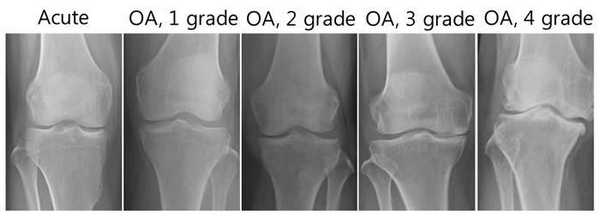

Стадии артрита коленного сустава на рентгене.